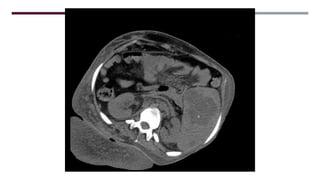

MASA SÓLIDO/QUISTICA

MESENTERIO/PERITONEO

LESION FOCAL PARED

ABDOMINAL

CALCIFICACION ESPLÉNICA